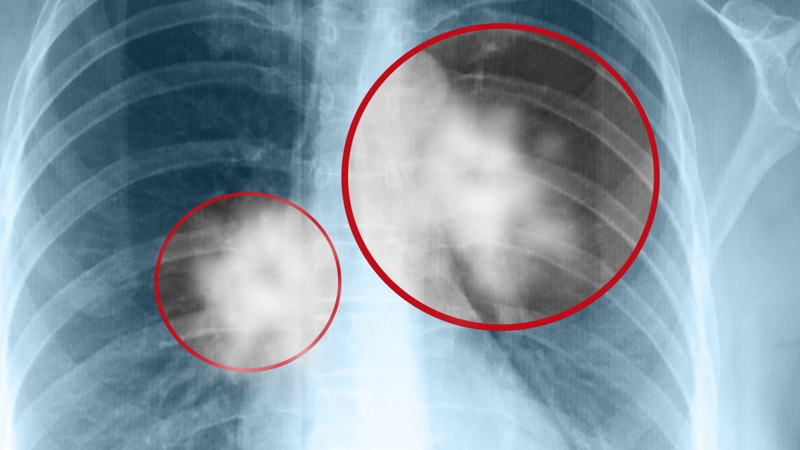

Mặc dù hình ảnh các khối u phổi trên phim chụp X quang khá đa dạng, nhưng thường gặp là các khối u mờ (thấy màu sáng trên phim), hình tròn, ranh giới có thể rõ hoặc không. Tùy theo vị trí của khối u sẽ được phân làm 2 loại chính:

• U phổi trung tâm: Đây là các khối u nằm quanh rốn phổi. Trên phim chụp X-quang là khối mờ vùng rốn phổi, bờ tua gai (nham nhở, dạng tia nắng mặt trời), ranh giới không rõ. Do bản chất xuất phát từ các phế quản lớn vùng rốn phổi nên có thể có hình ảnh xẹp thùy phổi của nhánh phế quản u xâm lấn.

• U phổi ngoại vi: Đây là các khối u nằm vùng ngoại vi của lá phổi. U phổi ngoại vi thường có các đặc điểm như hình tròn hoặc bầu dục, bờ và ranh giới rõ.

Ngoài việc phát hiện hình ảnh ung thư nguyên phát tại phổi vì phim X quang phổi còn có thể gặp hình ảnh tổn thương di căn từ ung thư tới các cơ quan khác. Bệnh lý này có biểu hiện các nốt mờ nhỏ, kích thước to nhỏ không đều, rải rác khắp trưởng phổi hai bên thường được gọi là hình ảnh “thả bóng”.

• Việc chụp X-quang nhằm giúp bác sĩ đánh giá sơ bộ các tổn thương tại phổi, có giá trị trong việc tầm soát ung thư phổi cho cộng đồng. Nếu hình ảnh trên phim X-quang có tổn thương và có dấu hiệu nghi ngờ ác tính (khối mờ vùng rốn phổi, bờ tua gai, ranh giới không rõ hay hình ảnh “thả bóng” hai trường phổi...), lúc này bác sĩ sẽ kết hợp thêm triệu chứng lâm sàng, chụp cắt lớp vi tính, xét nghiệm, sinh thiết u phổi để làm rõ chẩn đoán.